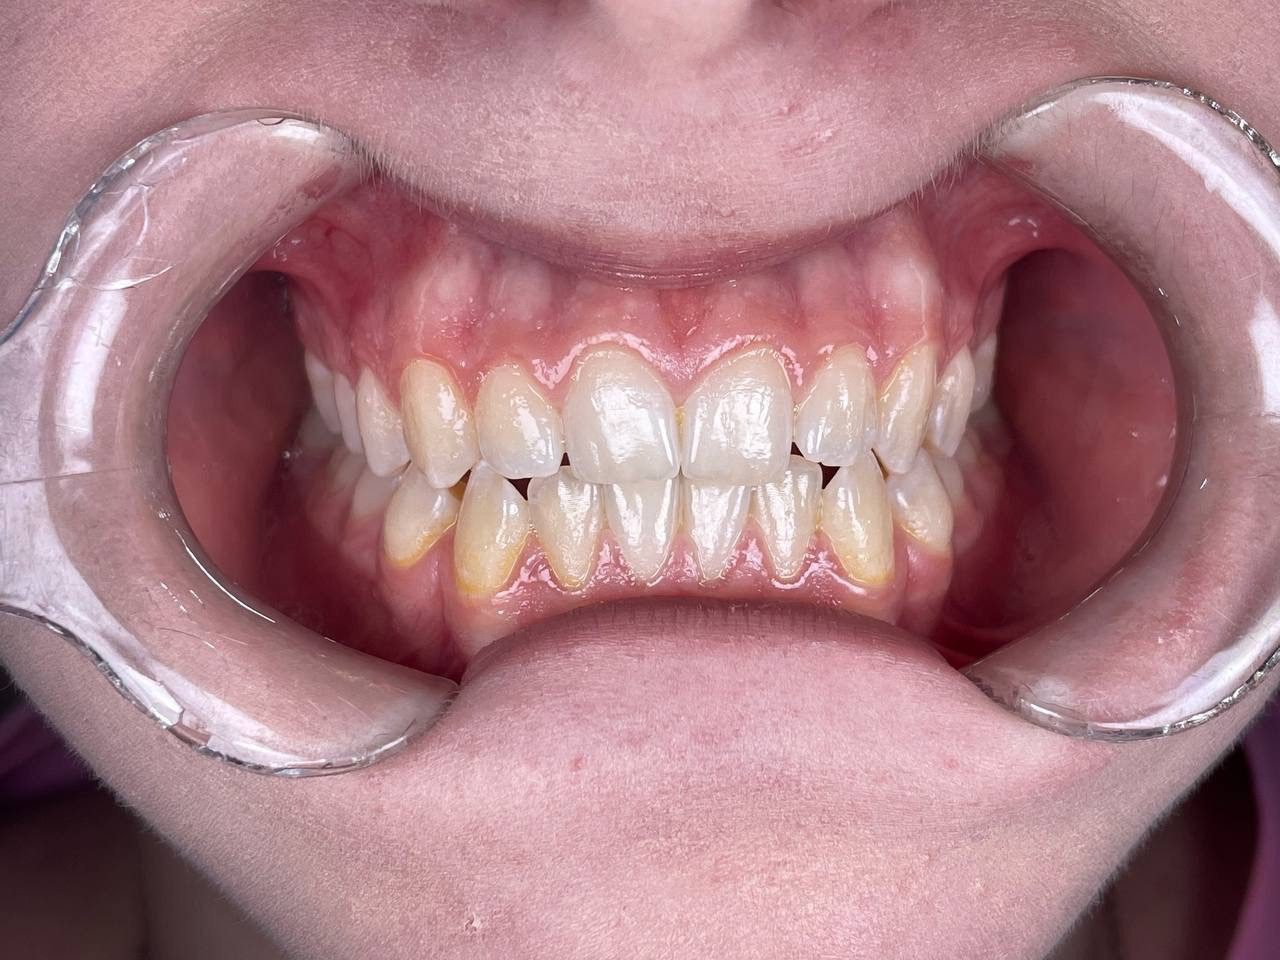

- Специализация: комплексная эстетика улыбки. Девиз врача – «Подарить красивую, идеальную улыбку!»